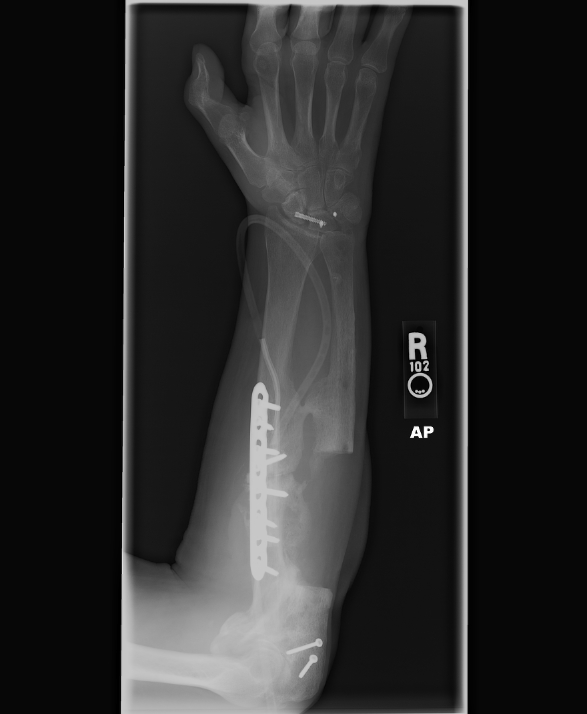

I have a couple of Robbie's latest X-rays. These show the missing 6 or 7 inches of bone in his arm........